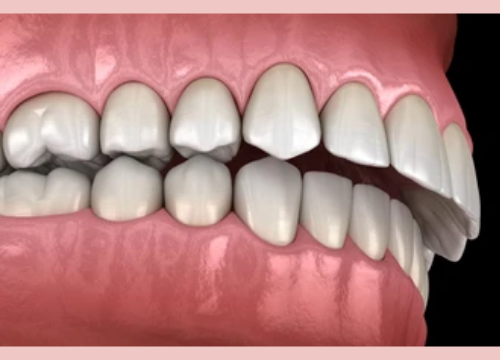

An overbite is the vertical overlap between the upper and lower front teeth when the back molars bite together. Overbites of up to 2 millimeters are considered normal and ideal. However, when there is an excessive overlap exceeding 3-4 mm, it is known as a deep bite.

The size, shape and relative positions of the upper and lower jaw is one of the factors influencing how the upper and lower teeth relate with each other. For example, if you have a small or underdeveloped lower jaw, it would be positioned further backwards compared to the upper jaw. This would lead to the upper anterior front teeth protruding over the lower teeth, resulting in a Class II malocclusion and possibly deep overbite too.

Difference Between Overbite and Overjet

An overbite is often mixed up with overjet or underbite as they tend to occur together. As a general guide, an overbite is when there is a vertical overlap between the upper front teeth that cover the lower teeth from top down. An overjet is however a horizontal overlap whereby the upper front teeth protrude out and over the lower front teeth.